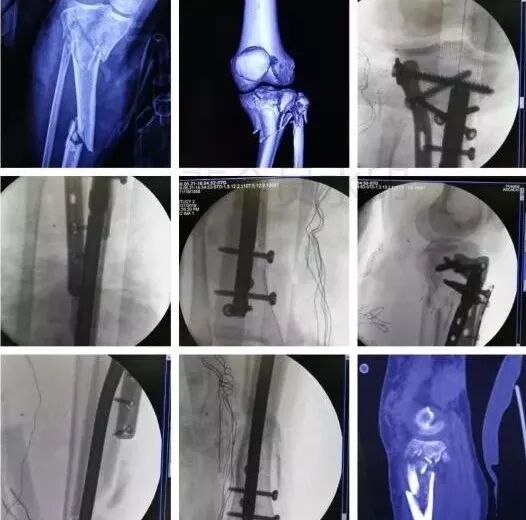

3)股骨远端骨折

图片

• 开放性骨折,伤及腘动脉,坐骨神经,紧急手术,超膝关节外支架。

• 单纯闭合骨折,内固定:钢板或逆行髓内钉。

5)胫骨近端骨折(平台)

• 高能量损伤,皮肤软组织条件差的,应延期手术。